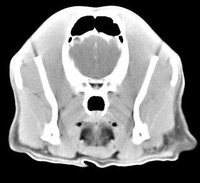

imágenes de TC en el perro | ||||||||||

ejemplo de imágenes de TC en el perro. Nótese la celulitis en la región parotídea izquierda | ||||||||||

Tomografía computarizada helicoidal |